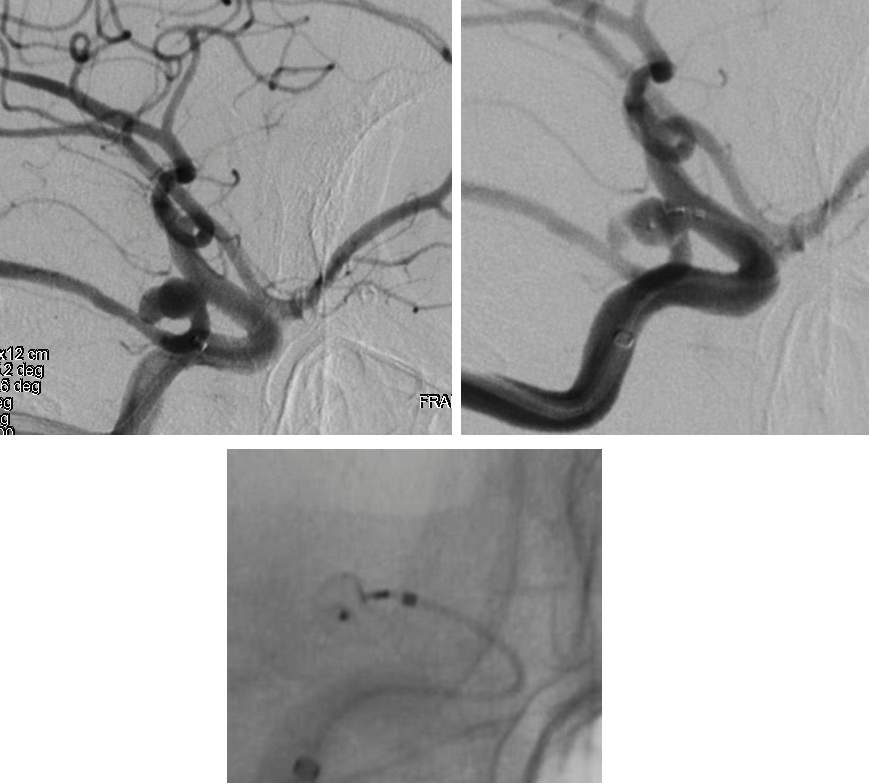

DSA:右侧颈内动脉后交通动脉起始段动脉瘤

侧位

调整解脱,后交通动脉通畅,子瘤内造影剂滞留

术后即刻造影